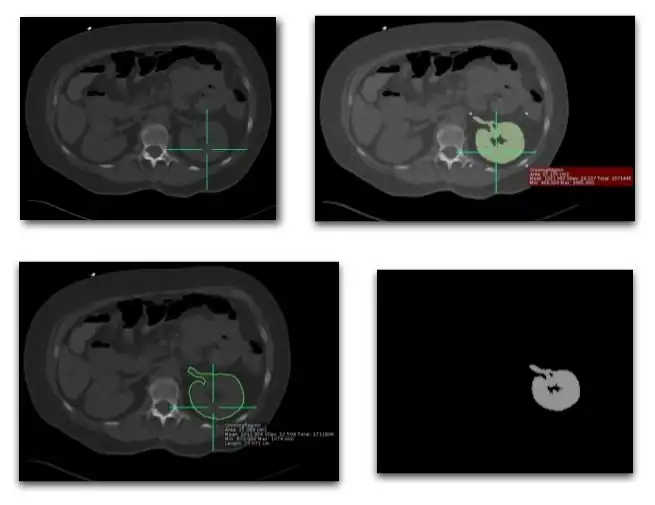

- Many forms of image analysis require the identification of structures and objects within an image. Image segmentation is the process of partitioning an image into distinct regions by grouping together pixels which belong to the same object. Two general approaches have been developed:

- Threshold Definition

- Here some property of an image is compared to a fixed or variable threshold on a pixel-by-pixel basis. A simple example is a grey-level threshold where a look-up table (LUT) of the form illustrated in the left hand panel of Figure 5.13.5 is applied, and where the value of the threshold, T, can be adjusted interactively.

- This is a useful technique when the image contains a single, well-defined object or group of objects of similar pixel value superimposed on a background with a substantially different pixel value. However, difficulties can arise with grey-level thresholding when objects are close together, e.g. cardiac chambers. Histogram analysis can be used as an alternative where pixel values are thresholded on the basis of their frequency of occurrence, as illustrated in the right hand panel of the figure. Other alternatives include thresholding colours when a CLUT is applied, monitoring the time of arrival of a tracer or contrast medium in a region of an image and analysis of the variation in pixel values in the neighbourhood of a pixel within an object of interest.

- Region Growth

- This technique exploits two characteristics of imaged objects:

- pixels for an object tend to have similar pixel values, and

- pixels for the same object are contiguous.

- A common technique is based on firstly defining a starting pixel in the object and then testing neighbouring pixels on the basis of a specific criterion for addition to a growing region. This criterion could be based on pixel value considerations, as in Figure 5.13.6 for instance, or on the anticipated size or shape of the object.

- Note that this approach can readily be extended to grow regions in three-dimensions when the image data consists of a set of contiguous tomographic slices.